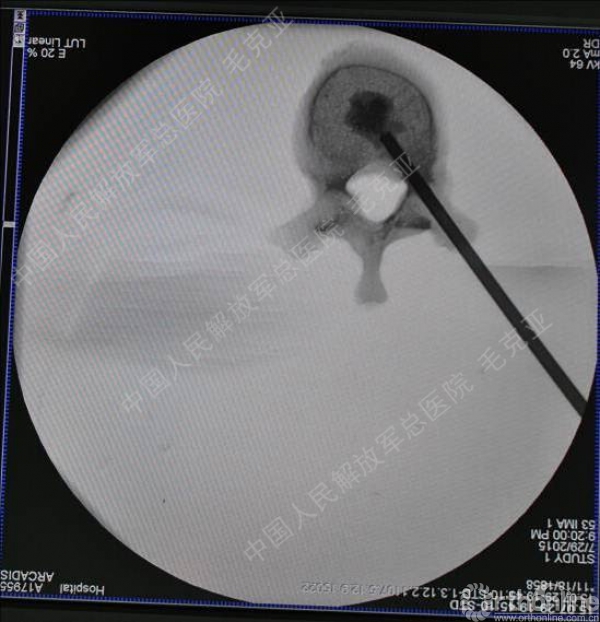

导语:随着社会老龄化的不断加速,骨质疏松性椎体压缩骨折作为一种普遍存在的老年骨科疾病已经成为现今骨科界的一个热点话题。传统的保守疗法治疗效果不佳,而现有的椎体增强技术又具有多种风险和缺陷。针对这种现状,中国人民解放军总医院毛克亚教授提供了一种新的解决方法。